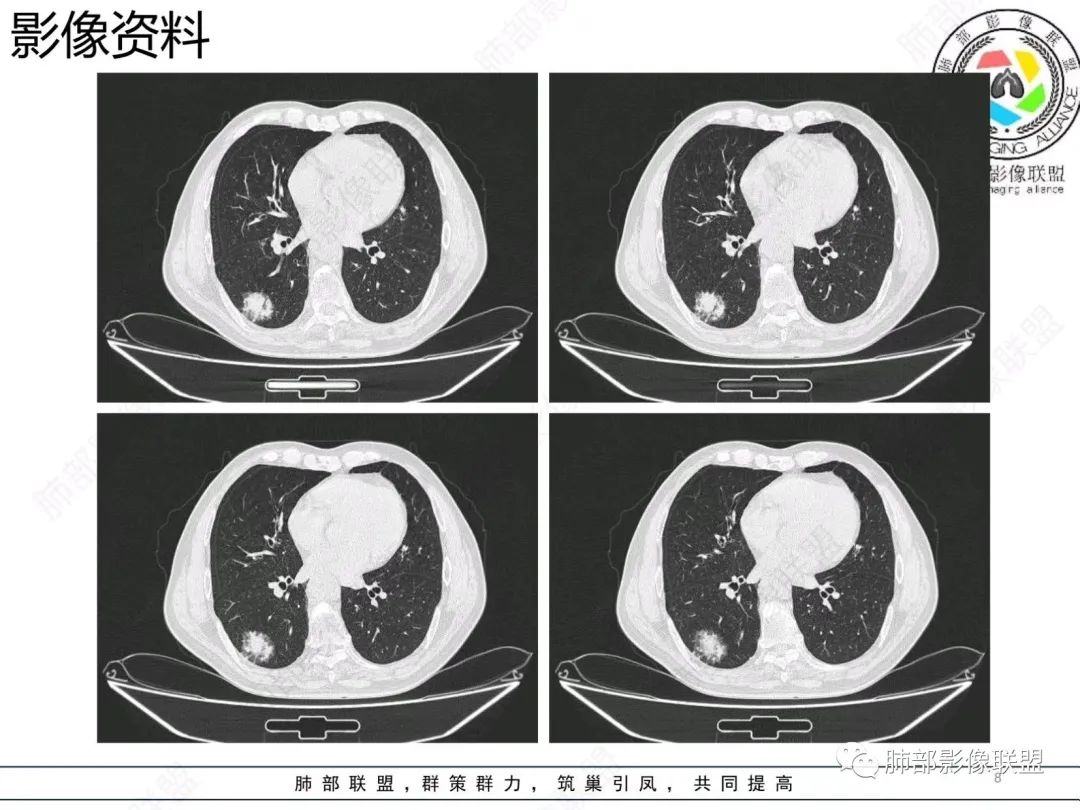

粘液腺癌CT表现:

1.结节型肺粘液腺癌以中老年女性多见,单发,发病部位常位于两下肺胸膜下(肺外周带)。

2.多数病灶具备典型恶性肿瘤征象,但是不典型者仍不少见。可有分叶和棘状突起,但较少出现典型毛刺征。强化程度不如一般的腺癌病灶那么显著。

3.病灶常呈圆形或不规则形,实性结节略多于混合磨玻璃结节,少见于纯磨玻璃结节;或囊实性结节影或肿块,密度混杂,部分可出现钙化;病灶边界可清楚,也可模糊,须与炎性结节鉴别;周围可有类圆形磨玻璃密度卫星灶;表现为实性结节病灶,收缩力可能表现不明显,较少胸膜凹陷或血管集聚,须与良性结节鉴别。

4.原发性肺粘液腺癌侵袭力相对较低,发展慢;病灶较少破坏支气管及血管,可表现为血管造影征及空气支气管征。较少胸膜侵犯,也较少肺门纵隔淋巴结转移。

病理影像:

1.病理基础:肺原发性粘液腺癌的肿瘤细胞产生大量粘液,聚集于细胞内,破入细胞间隙甚至肺泡、末梢细支气管,致使病灶密度增高呈混合磨玻璃或实性结节。

2.粘液的直接扩散和漂移,致使病灶边界模糊和病灶呈多灶性生长。

3.粘液的重力效应致使病灶常位于胸膜下或叶间胸膜附近。

4.病灶内气管、血管破坏不明显,可出现血管造影征及空气支气管征;也提示病灶侵袭力较低。

5.粘液的张力(占位效应)常可抵消病灶收缩力,致使病灶收缩力表现常较弱。